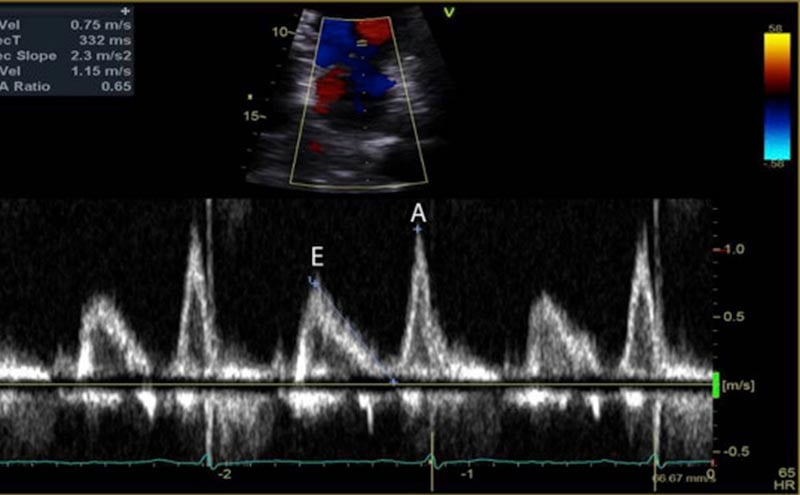

Fig 1. Mitral inflow velocity

The mitral inflow velocity tracing produces a graph of velocity over time. (Figure 3) The two upward deflections occur during diastole and are known as the E wave (for “early” diastole during which passive filling occurs across a pressure gradient) and the A wave (for “atrial” contraction), and the downward deflection occurs during systole. The tissue doppler tracing produces a similar graph but the two downward deflections occur during diastole and upward deflections occur during systole. (Figure 4) These two downward tissue doppler deflections are known as the e’ wave and the a’ wave.

Fig 3. Mitral Inflow Velocity Tracing